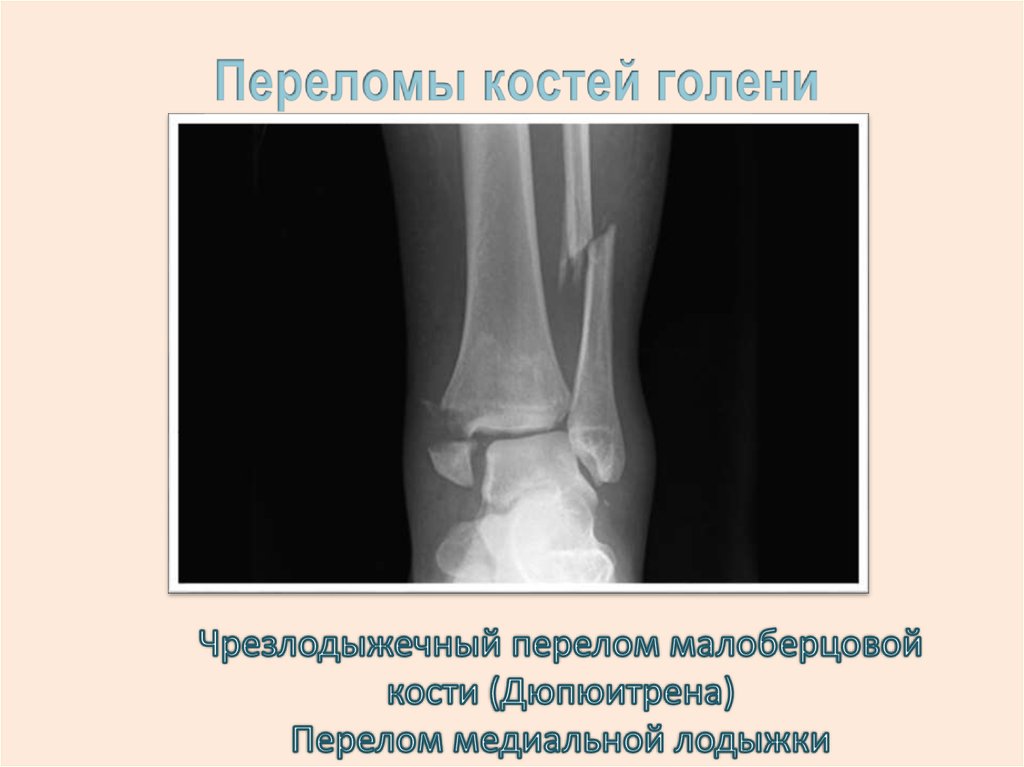

21.

ВЫВИХ – ПОЛНОЕ нарушение

суставных соотношений